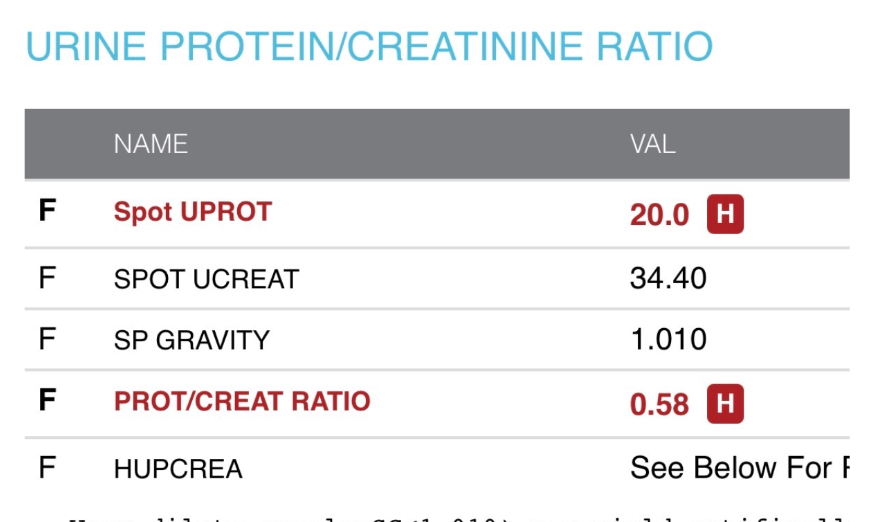

The Tomanka family has officially reached the 31-week mark of baby girl Tomanka, just one week shy of the mark that Liam was welcomed into the world. Karsen and Evie remember all too well the nightmare of 2025, and they are all holding each other closely through this time. Kate's health has increasingly declined, with the complications of preeclampsia, increased swelling, incompetent valves of the saphenous vein affecting her pelvic area through her ankle of her left leg, severe iron deficiency, low amniotic fluid, and a watch for baby girl's growth due to the functioning of the placenta, affected by preeclampsia, measuring baby at the 10th percentile as of last week.